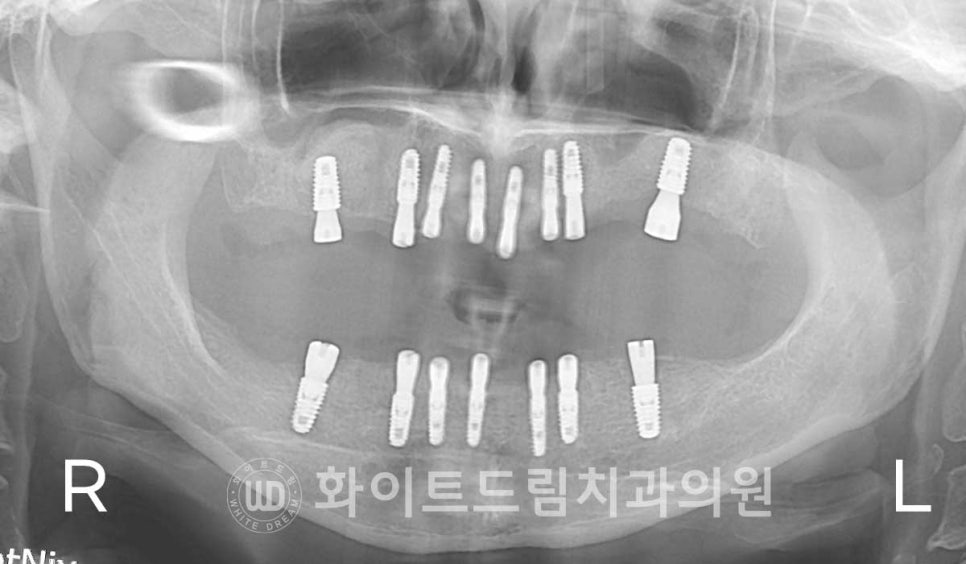

(강남역화이트드림치과 / 상악 임플란트 수술 : 24.08.24)

환자분의 x-ray 사진을 보면

어떤 임플란트는 잇몸뼈 안에 있고,

어떤 임플란트는 잇몸 밖을 노출되고 있음을 확인하실 수 있는데

이 차이가 바로 1차 수술과 2차 수술의 차이점입니다.

임플란트는 최대한 자극을 받지 않으면서

골 유착 과정을 밟는 것이 예후가 좋습니다.

그래서 많은 양의 뼈이식재가 들어간 부위는 새로운 뼈가 형성되고

이 뼈와 임플란트가 잘 유착될 수 있도록 임플란트를 잇몸뼈 안에 둔 후

봉합하게 됩니다. (= 1차 수술)